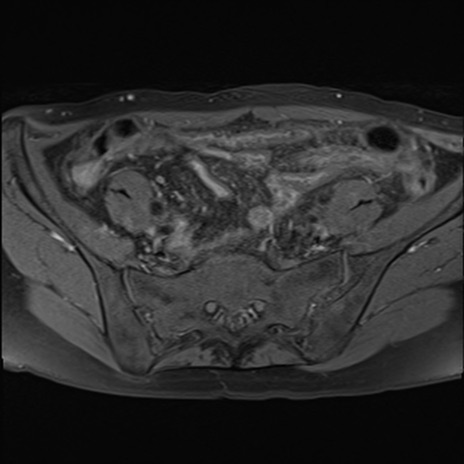

症例39 脂肪抑制T1WI(横断像)

MRI(4日後)

T1WI(横断像)